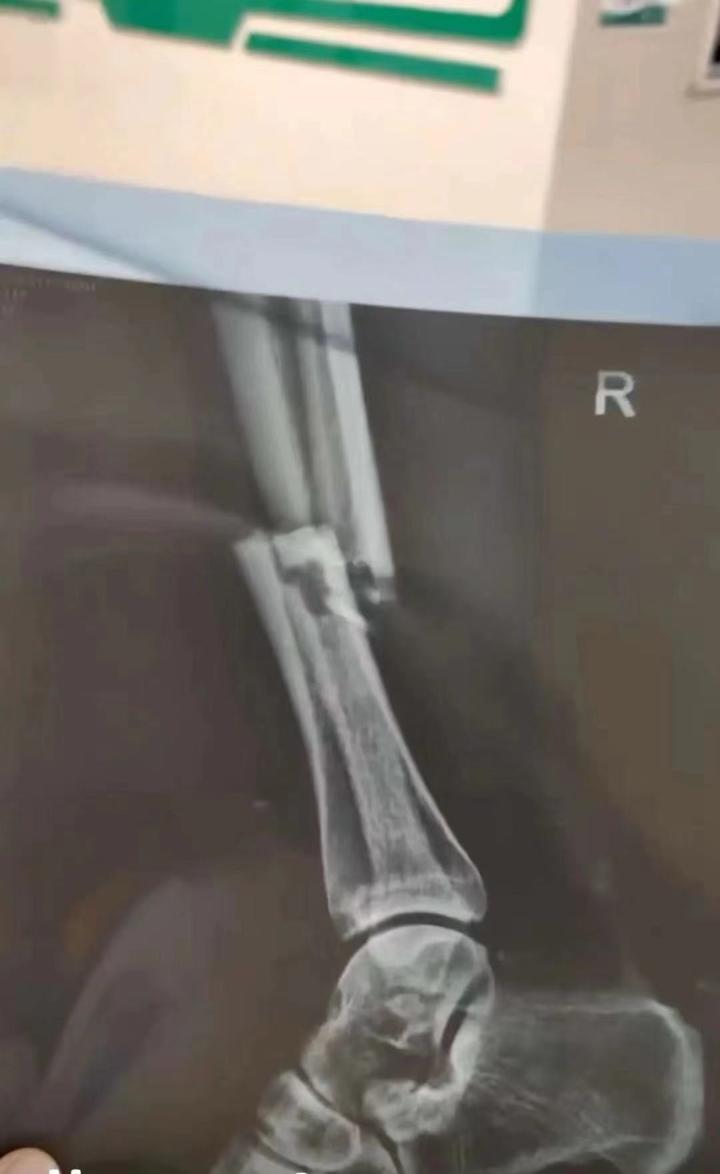

网传x光片显示,帕尔曼江右腿骨折

网传照片显示,帕尔曼江右腿拍片诊断结果是骨折,这就意味着他新赛季将缺席前半段大部分比赛。加上此前被禁赛7场的布格拉汗,以及遭遇十字韧带伤势的杨浩,广州队新赛季还未开始已损失三名前场重要球员。